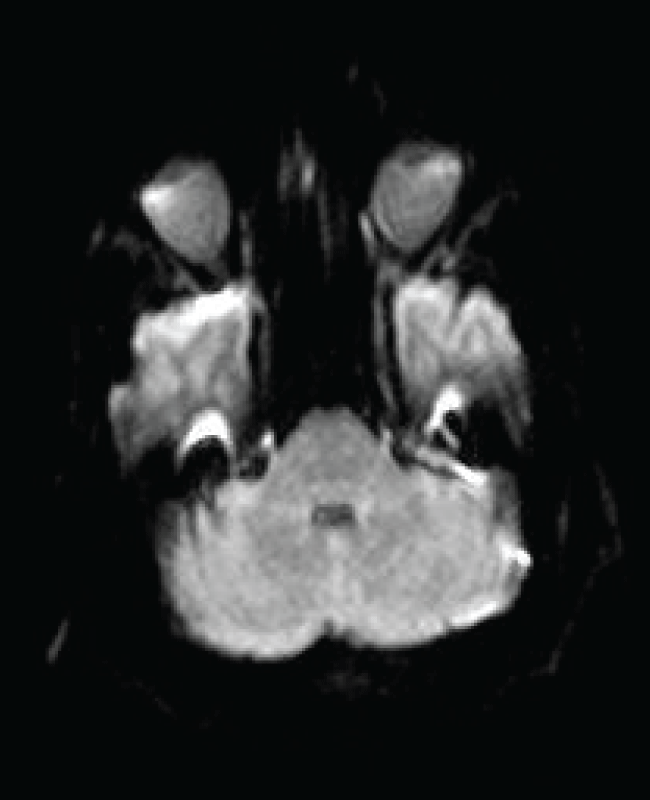

On hospital day 21, an MR brain demonstrated hyperintense signal on FLAIR (Figure 1) and T2 sequences in both cerebellar dentate nuclei, dorsal pons and central tegmental tract. Diffusion weighted images (DWIs) showed bright signal in both cerebellar dentate nuclei (Figure 2) with corresponding high apparent diffusion coefficient (ADC) consistent with vasogenic edema. The lesions did not demonstrate contrast enhancement.

Figure 2: Axial diffusion weighted image (DWI) shows bright signal (restricted diffusion) in both dentate nuclei of the cerebellum (arrow). Apparent diffusion coefficient map (ADC) demonstrate a corresponding area of high ADC consistent with vasogenic edema.

Neurology consultation found the patient to be alert, oriented with intact cognition but very dysarthric speech. Cranial nerve exam was significant for coarse horizontal nystagmus to both left and right lateral gaze. He was confined to bed and unable to feed himself because of incapacitating truncal and appendicular ataxia. Based on the characteristic MR findings of hyperintense signal most notable in both cerebellar dentate nuclei, a diagnosis of metronidazole-induced cerebellar toxicity was made. Metronidazole was promptly discontinued. Lumbar puncture was not performed due to an elevated INR secondary to his hepatic dysfunction.

On FLAIR and T2 weighted images, common findings include hyperintense lesions of the cerebellar dentate nuclei, midbrain, dorsal pons, corpus callosum, and cerebral white matter. A pattern consistent with vasogenic edema is usually identified with bright signal on diffusion-weighted images (DWI) and high apparent diffusion coefficient (ADC). These MR findings are most conspicuous in bilateral cerebellar dentate nuclei and resolve in conjunction with clinical improvement upon drug discontinuation. Permanent residual neurologic deficits have been reported highlighting the need for prompt recognition.